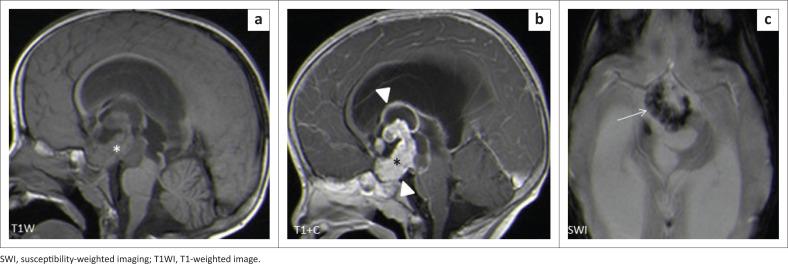

A total of 931 MRI brain scans were performed. One hundred and seven scans met the inclusion criteria, of which 92 were primary brain tumours and 15 were inflammatory masses. The majority were females (56%). The mean age was 12 ± 4.52 (range of 3-18 years). The most common presenting symptom was seizures (70/107, 65.4%). We categorised the masses according to supra- and infratentorial compartments. The most common site for masses was the supratentorial compartment ( = 56, 52%). The most common masses in the supratentorial compartment were craniopharyngiomas (14/45, 31.1%), whilst in the infratentorial compartment, the most common masses were medulloblastomas (24/47, 51.1%).

共进行了931次脑部MRI扫描。107次扫描符合纳入标准,其中92次为原发性脑肿瘤,15次为炎性肿块。大多数为女性(56%)。平均年龄为12±4.52岁(范围为3 - 18岁)。最常见的首发症状是癫痫发作(70/107,65.4%)。我们根据幕上和幕下腔室对肿块进行分类。肿块最常见的部位是幕上腔室(= 56,52%)。幕上腔室最常见的肿块是颅咽管瘤(14/45,31.1%),而在幕下腔室,最常见的肿块是髓母细胞瘤(24/47,51.1%)。